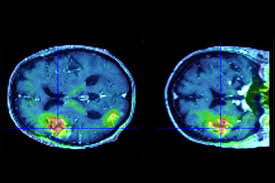

Toulouse A Purpan On Traite Plus De 2 600 Avc Par An Ladepeche Fr

Toulouse A Purpan On Traite Plus De 2 600 Avc Par An Ladepeche Fr from images.ladepeche.fr